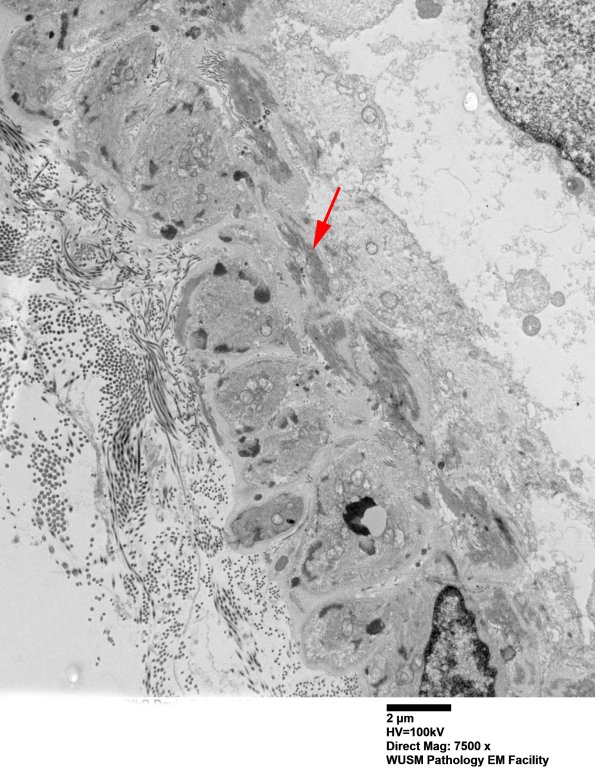

The following ultrastructural examination presents individual small arteriolar size vessels in groups11C1A-C, 11C2A-E, etc., based on several magnifications focusing on GOMs of individual vessels. ---- 11C1A-C A portion of the wall of the large vessel shown in image #11B1,2. ---- 11C1A There is a portion of the muscle wall and internal elastic lamina (arrow). (electron micrograph)